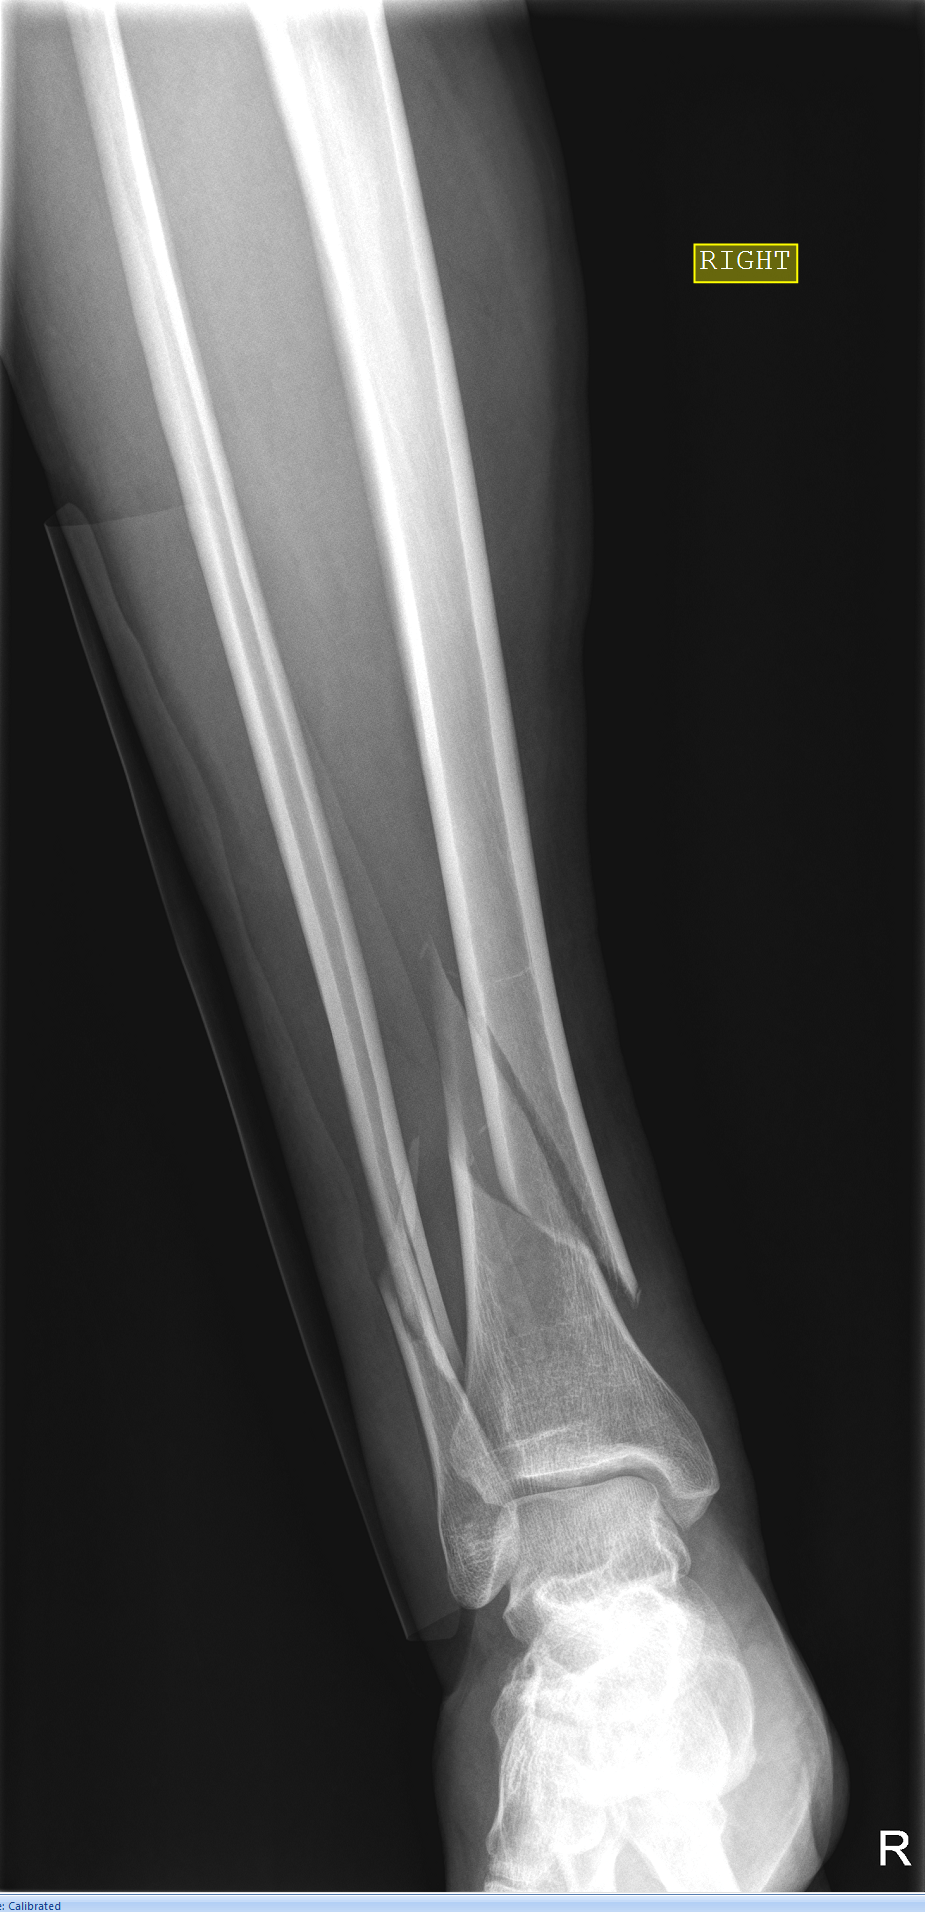

Spiral Fracture Of The Distal Tibia . High association of posterior malleolus fractures with spiral distal tibia fractures A spiral fracture, also known as torsion fracture, is a type of complete fracture that occurs due to a rotational, or twisting, force. Pediatric tibial shaft fractures are the third most common long bone fracture in children. Tibia fractures can also be closed or. The long bones are the bones of the body that are longer than they are wide. Spiral fracture often caused by a twisting force, this break causes a spiraling line to appear on the bone and may become unstable over time. Diagnosis can be confirmed with plain radiographs of the tibia. A spiral fracture happens when a long bone is torn in half by a twisting force or impact. Spiral fractures are complete fractures of long bones that result from a rotational force applied to the bone.

The spiral tibia fracture line was contiguous with the PMF in this

The spiral tibia fracture line was contiguous with the PMF in this Spiral Fracture Of The Distal Tibia High association of posterior malleolus fractures with spiral distal tibia fractures Tibia fractures can also be closed or. Spiral fracture often caused by a twisting force, this break causes a spiraling line to appear on the bone and may become unstable over time. Pediatric tibial shaft fractures are the third most common long bone fracture in children. Spiral fractures are. Spiral Fracture Of The Distal Tibia.

Right distal third spiral tibia fracture (a) with normal appearing Spiral Fracture Of The Distal Tibia Pediatric tibial shaft fractures are the third most common long bone fracture in children. Diagnosis can be confirmed with plain radiographs of the tibia. High association of posterior malleolus fractures with spiral distal tibia fractures Tibia fractures can also be closed or. The long bones are the bones of the body that are longer than they are wide. Spiral fracture. Spiral Fracture Of The Distal Tibia.